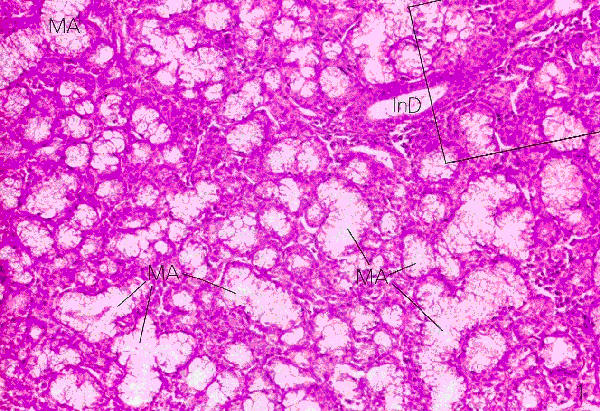

Fig 13.17

Wheater p. 246

Serous Secretory Units

- The cells of the units appear triangular while the units themselves are round

- The nuclei are round and located close to the cell bases

- The cytoplasm is basophilic near the base (where the nucleus is located) and the rest is acidophilic (due to the secretory vesicles)

- The units are surrounded by myoepithelial cells which are located between the cells of the unit and the basement membrane

- The lumen of the unit is small and inconspicuous